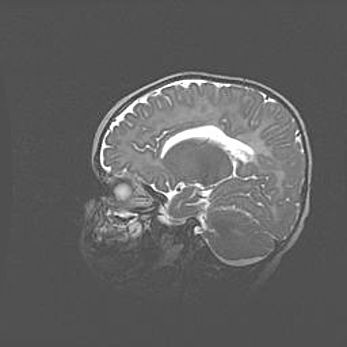

Сообщающаяся гидроцефалия. Кистозная энцефаломаляция головного мозга.

Возраст: 3 месяца 4 дня

Вес: 3100 г

Пол: женский

Окружность головы: 34 см

Срок гестации: 31 неделя

Кистозная энцефаломаляция головного мозга - одна из форм поражения головного мозга в детском возрасте. Характеризуется возникновением множественных и распространённых кист в коре, белом веществе и подкорковых образованиях головного мозга у плодов, новорождённых и детей раннего возраста. Развитие кистозной энцефаломаляции связано с внутриутробной асфиксией и гипотонией, родовой травмой, тромбозом синусов, пороками развития сосудов, инфекциями, сепсисом и другими причинами. Наиболее значимые инфекционные агенты: вирусы простого герпеса, цитомегалии, краснухи, токсоплазмы, энтеробактерии, золотистый стафилококк и другие.